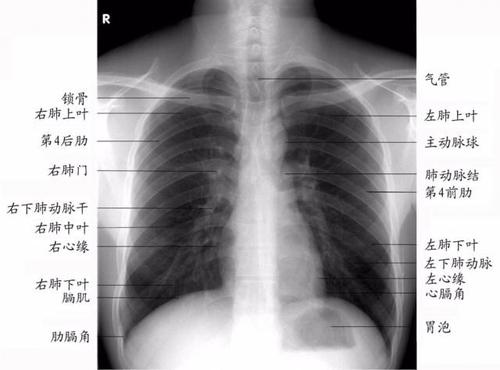

正常女性胸片

正常女性胸片,正常胸片和异常胸片

正常x线胸片表现